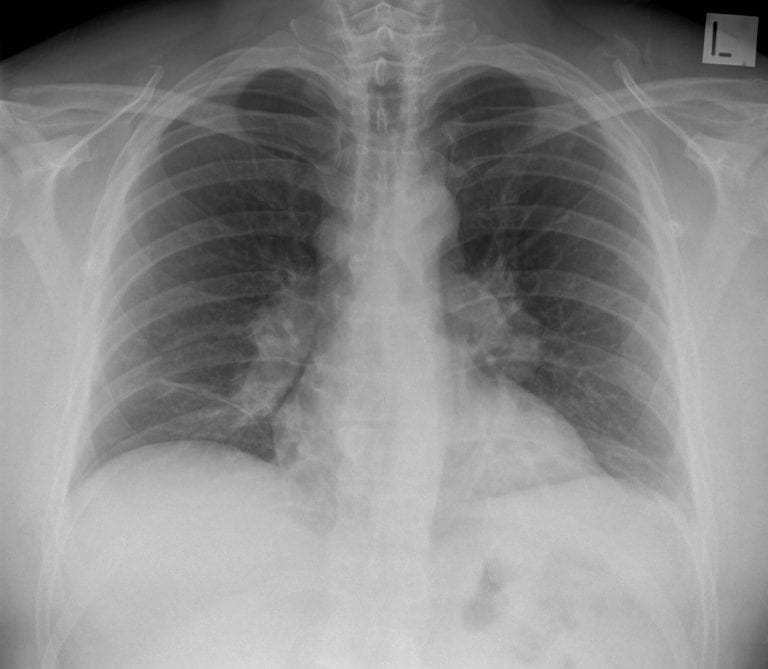

CXR Case 029

A 32 year old old male presents with a dry cough, malaise and arthralgia

Describe and interpret this CXR

There is bilateral hilar adenopathy and bands of atelectasis in both lung bases.

*Lung parenchyma looks normal.

This is sarcoidosis (stage 1 on radiological classification)

*Important differentials to consider would be lymphoma and TB *

Lymph node biopsy (these days guided by endobronchial ultrasound) demonstrating non-caseating granuloma is needed to secure the diagnosis

Once the diagnosis is secure, sarcoidosis that is not causing organ damage does not necessary need treatment, ~85% of cases at this stage will resolve spontaneously over 8-12 months.